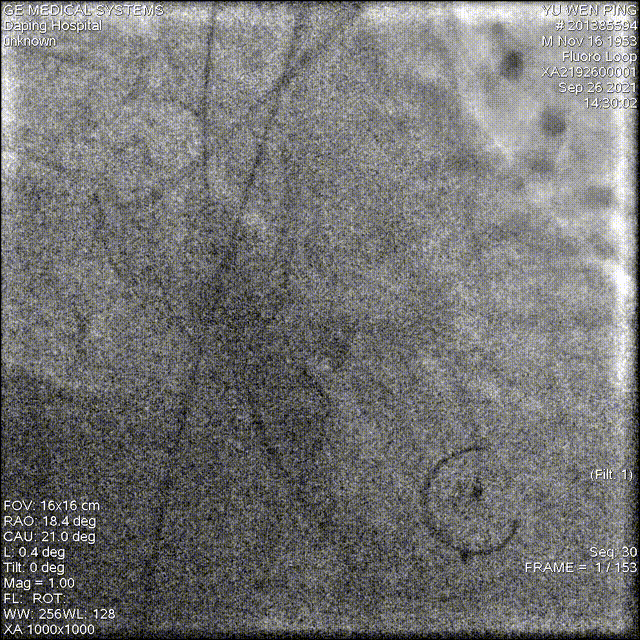

释放成功,但存在中度瓣周漏,经20mm球囊后扩,造影见微量瓣周漏,较前明显好转

术后结果

术后造影及超声探查未见反流,跨瓣压差由术前65mmHg降为3mmHg,术中及术后未出现相关并发症,手术圆满完成。